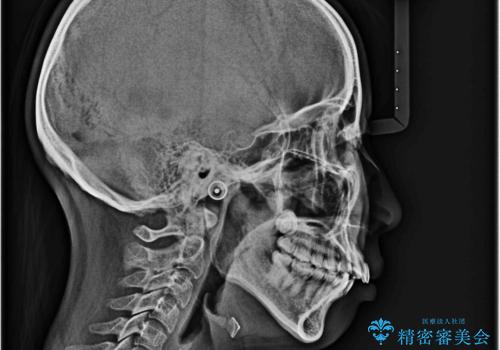

- 前歯が出ていることと、下の歯のがたがたで歯磨きがしにくいことを主訴に来院されました。

マウスピース矯正の希望があり、ワイヤーリカバリの可能性を伝えたうえでインビザライン抜歯矯正を行っています。

来院が途中途絶えたこともあり、4年ぐらい期間がかかりましたが、インビザラインだけで治療を終えることができました。